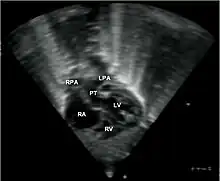

•Echocardiogram: An echocardiogram is an ultrasound of the heart that accurately assesses the heart’s structure and function, and can show the specific features of TGA, if present. This imaging modality allows for the definitive diagnosis of TGA to be made.[3]

Abbreviations: RA=right atrium, RV=right ventricle, LV=left ventricle, PT=pulmonary trunk, LPA and RPA=left and right pulmonary artery.